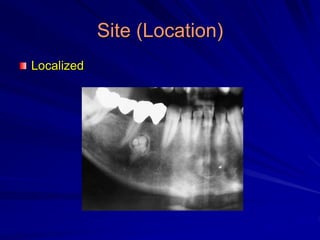

Site (Location)

Localized